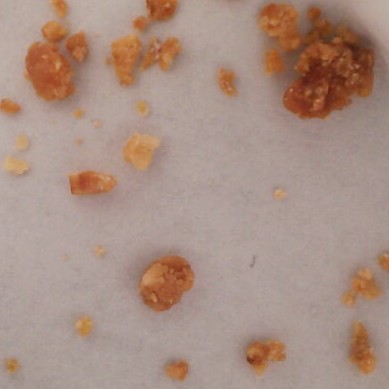

Image Details Sold as Results Test strip results Notes Location Date Category: OpioidDescription: White ChunkSold as: HydromorphoneResult: Lactose Hydromorphone Uncertain Oil

Fentanyl: NegativeBenzodiazepine: NegativeNotes: Vancouver, BC 01/18/2025 Category: OtherDescription: White PowderSold as: alpha-GPCResult: Fentanyl: NegativeBenzodiazepine: NegativeNotes: This sample shares similarities with our reference for alpha-GPC, but could not be confirmedVancouver, BC 01/18/2025 Category: DepressantDescription: Light Blue ChunkSold as: AlprazolamResult: Fentanyl: NegativeBenzodiazepine: PositiveNotes: The uncertain match in this sample shares similarities with a number of benzodiazepines, but can not be confirmed as such.Vancouver, BC 01/18/2025 Category: OtherDescription: White PowderSold as: ModafinilResult: Fentanyl: NegativeBenzodiazepine: NegativeNotes: Vancouver, BC 01/18/2025 Category: PsychedelicDescription: White PowderSold as: KetamineResult: Fentanyl: NegativeNotes: Vancouver, BC 01/18/2025 Category: DepressantDescription: White PowderSold as: PhenibutResult: Fentanyl: NegativeBenzodiazepine: NegativeNotes: Vancouver, BC 01/18/2025 Category: PsychedelicDescription: Light Grey CrystalSold as: MDMAResult: Fentanyl: NegativeNotes: Vancouver, BC 01/18/2025 Category: PsychedelicDescription: Colourless CrystalSold as: KetamineResult: Fentanyl: NegativeNotes: Vancouver, BC 01/18/2025 Category: OpioidDescription: White TabletSold as: HydromorphoneResult: Lactose Hydromorphone Uncertain Oil